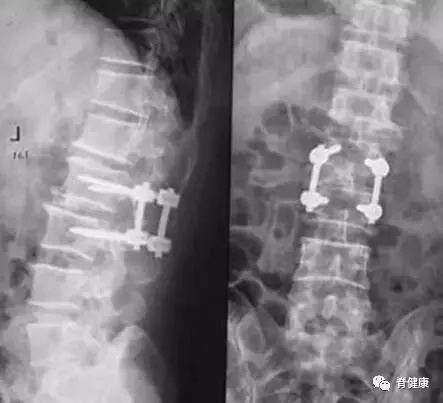

单纯的椎间盘突出并不对我们的生活造成影响 , 椎间盘突出会使得脊柱的灵活性变差 , 椎间盘突出的手术治疗也是将髓核取出 , 固定椎体使其不能活动 。 人体的椎体节数较多 , 单一的椎间盘无法活动 , 并不能很大程度的影响脊柱的灵活性 。

本文图片

椎间盘手术钉

手术治疗

对反复发作 , 经非手术治疗无效 , 或是出现脊髓压迫症状者 , 应及早行手术治疗 。 目前以路突出髓核摘除、人工椎间盘置换为主 。